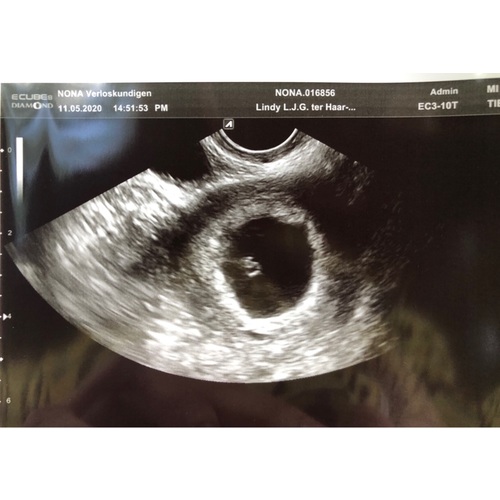

Deze was de mijne op 5w5, 2 vruchtzakjes en geen kindjes. Inmiddels toch al 23 weken zwanger van 2 meisjes. Laat de moed niet zakken!